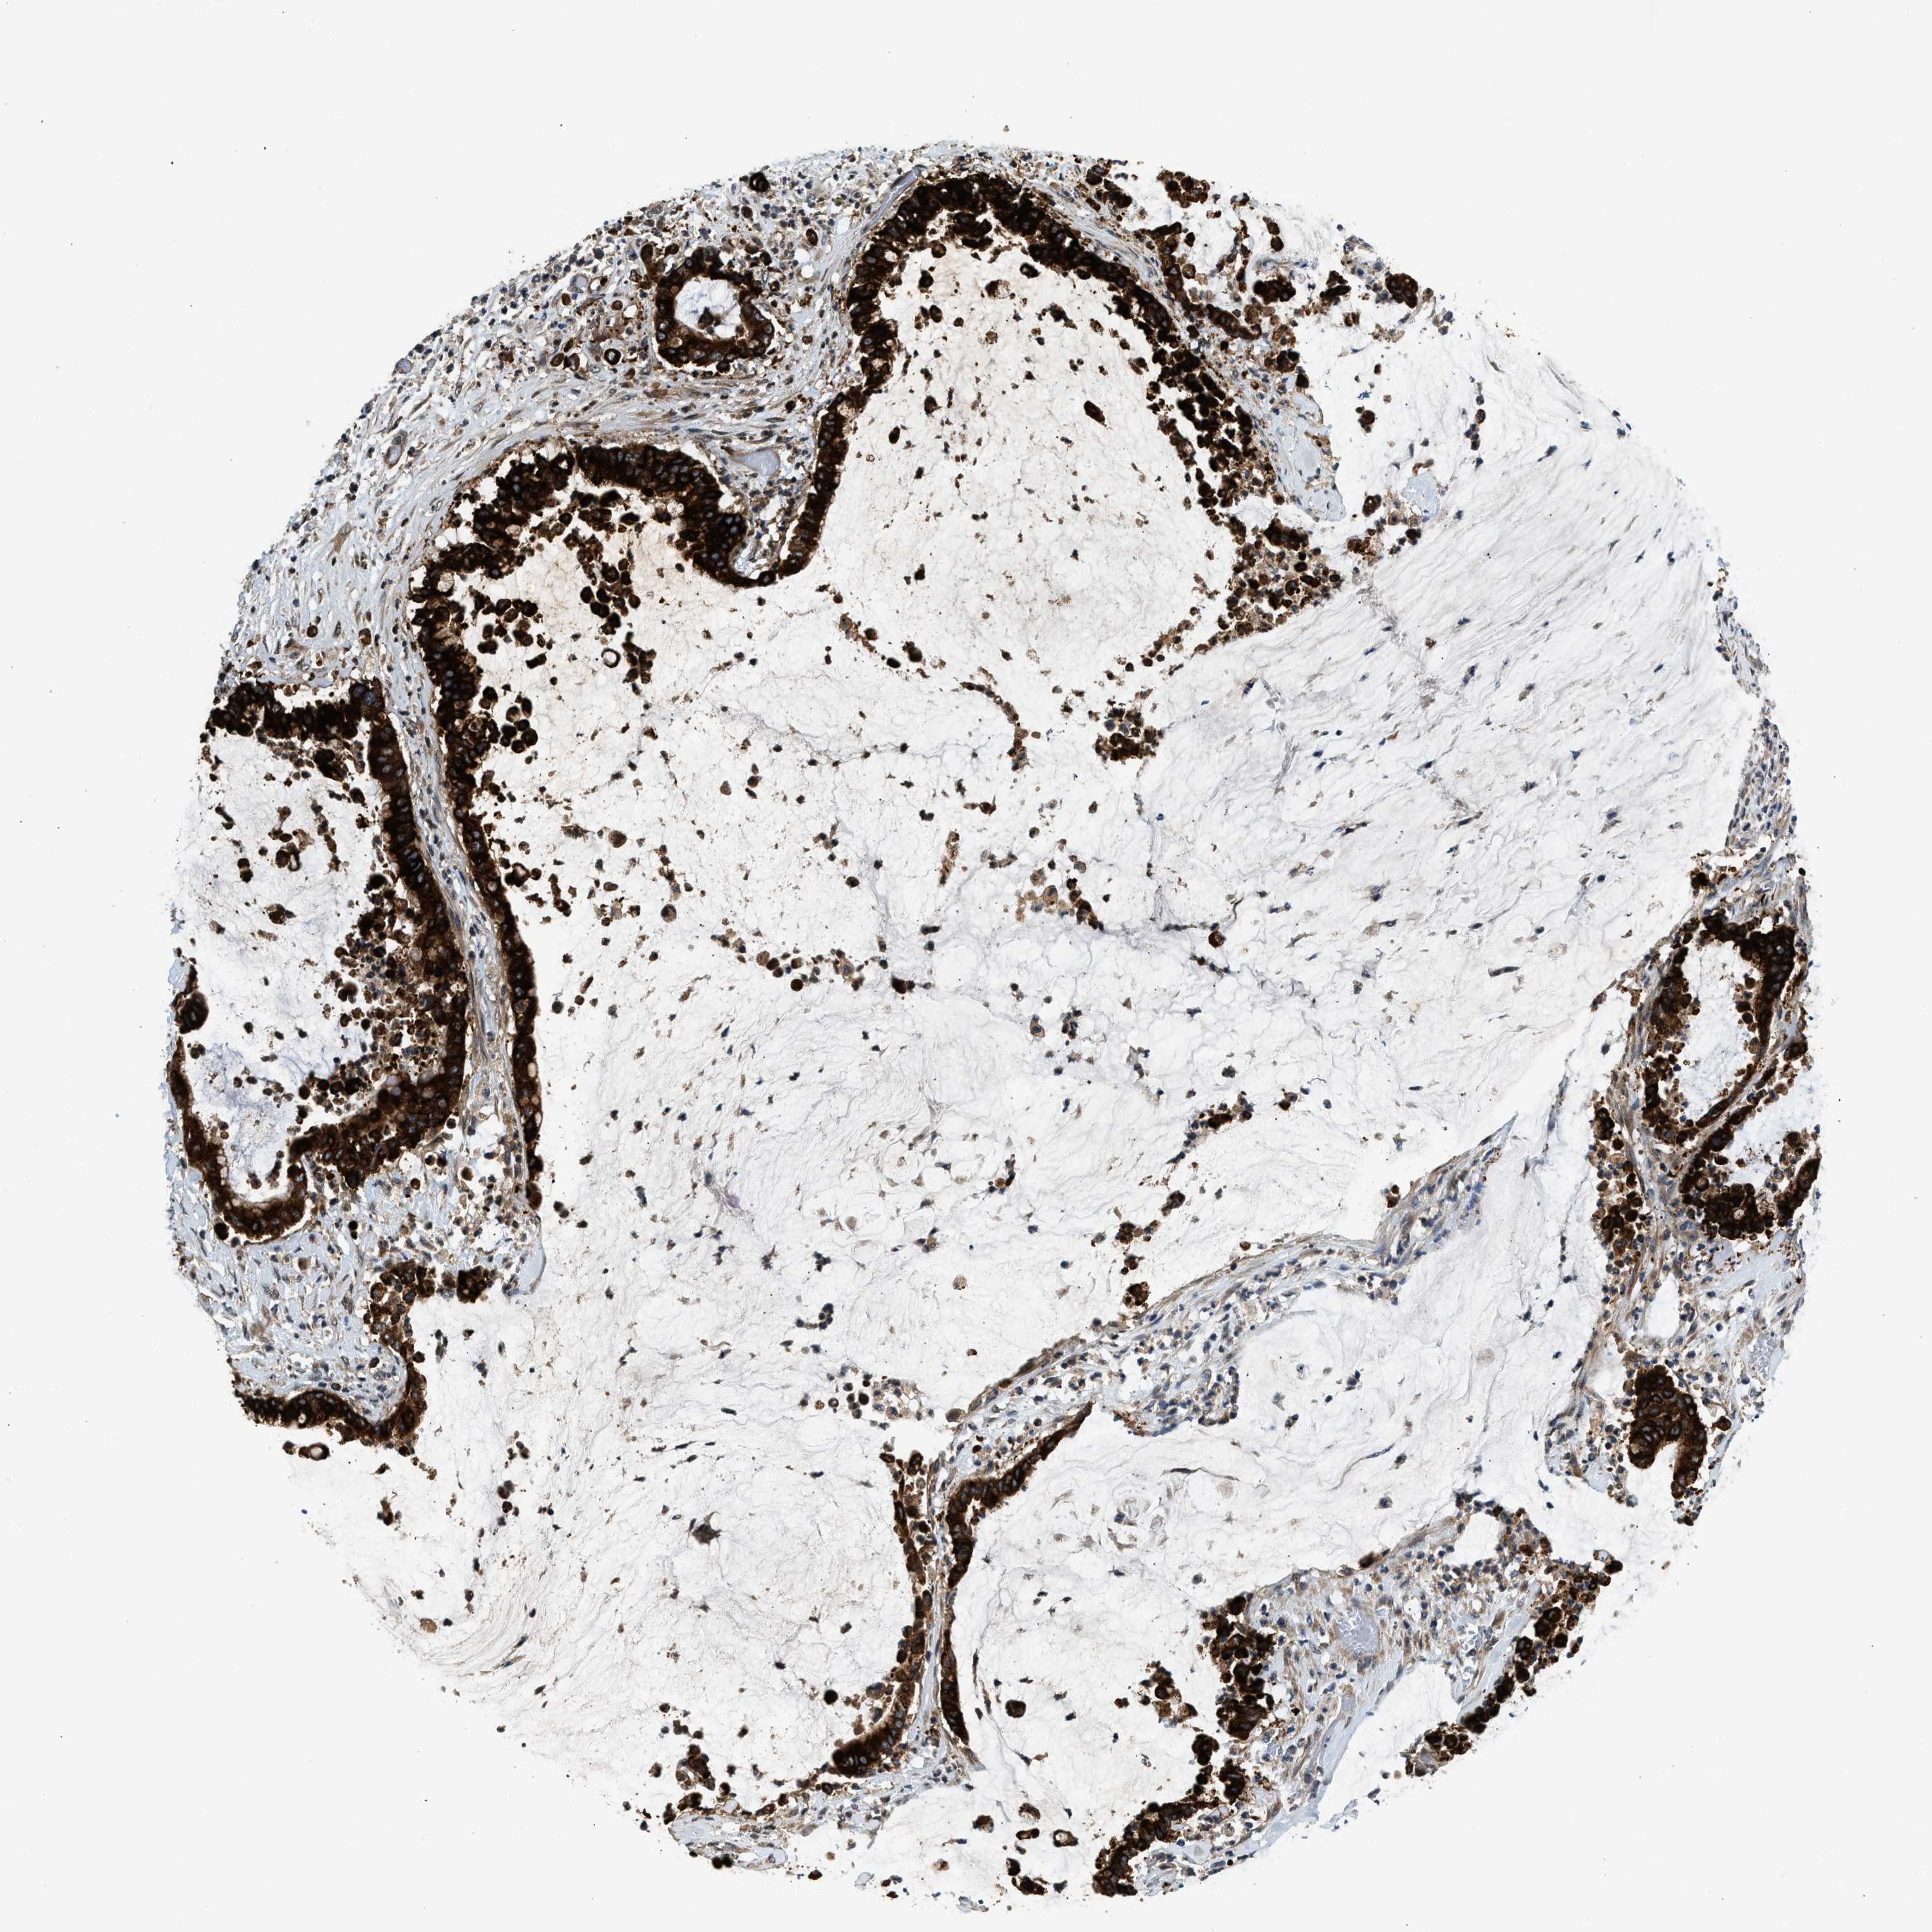

PANCREATIC CANCER - Protein expressioni

A mouse-over function shows sample information and annotation data. Click on an image to view it in a full screen mode. Samples can be filtered based on level of antibody staining by selecting one or several of the following categories: high, medium, low and not detected. The assay and annotation is described here.

Note that samples used for immunohistochemistry by the Human Protein Atlas do not correspond to samples in the TCGA dataset.

Antibody stainingi

Antibody staining in the annotated cell types in the current human tissue is reported as not detected, low, medium, or high, based on conventional immunohistochemistry profiling in selected tissues. This score is based on the combination of the staining intensity and fraction of stained cells.

Each image is clickable and will lead to virtual microscopy that enables deeper exploration of all samples and also displays staining intensity scores, fraction scores and subcellular localization as well as patient and tissue information for each sample.

Antibody HPA003539

Antibody CAB018374

Staining

High

Medium

Low

Not detected

Intensity

Strong

Moderate

Weak

Negative

Quantity

>75%

75%-25%

<25%

None

Location

Nuclear

Cytoplasmic/membranous

Cytoplasmic/membranous,nuclear

Adenocarcinoma, NOS